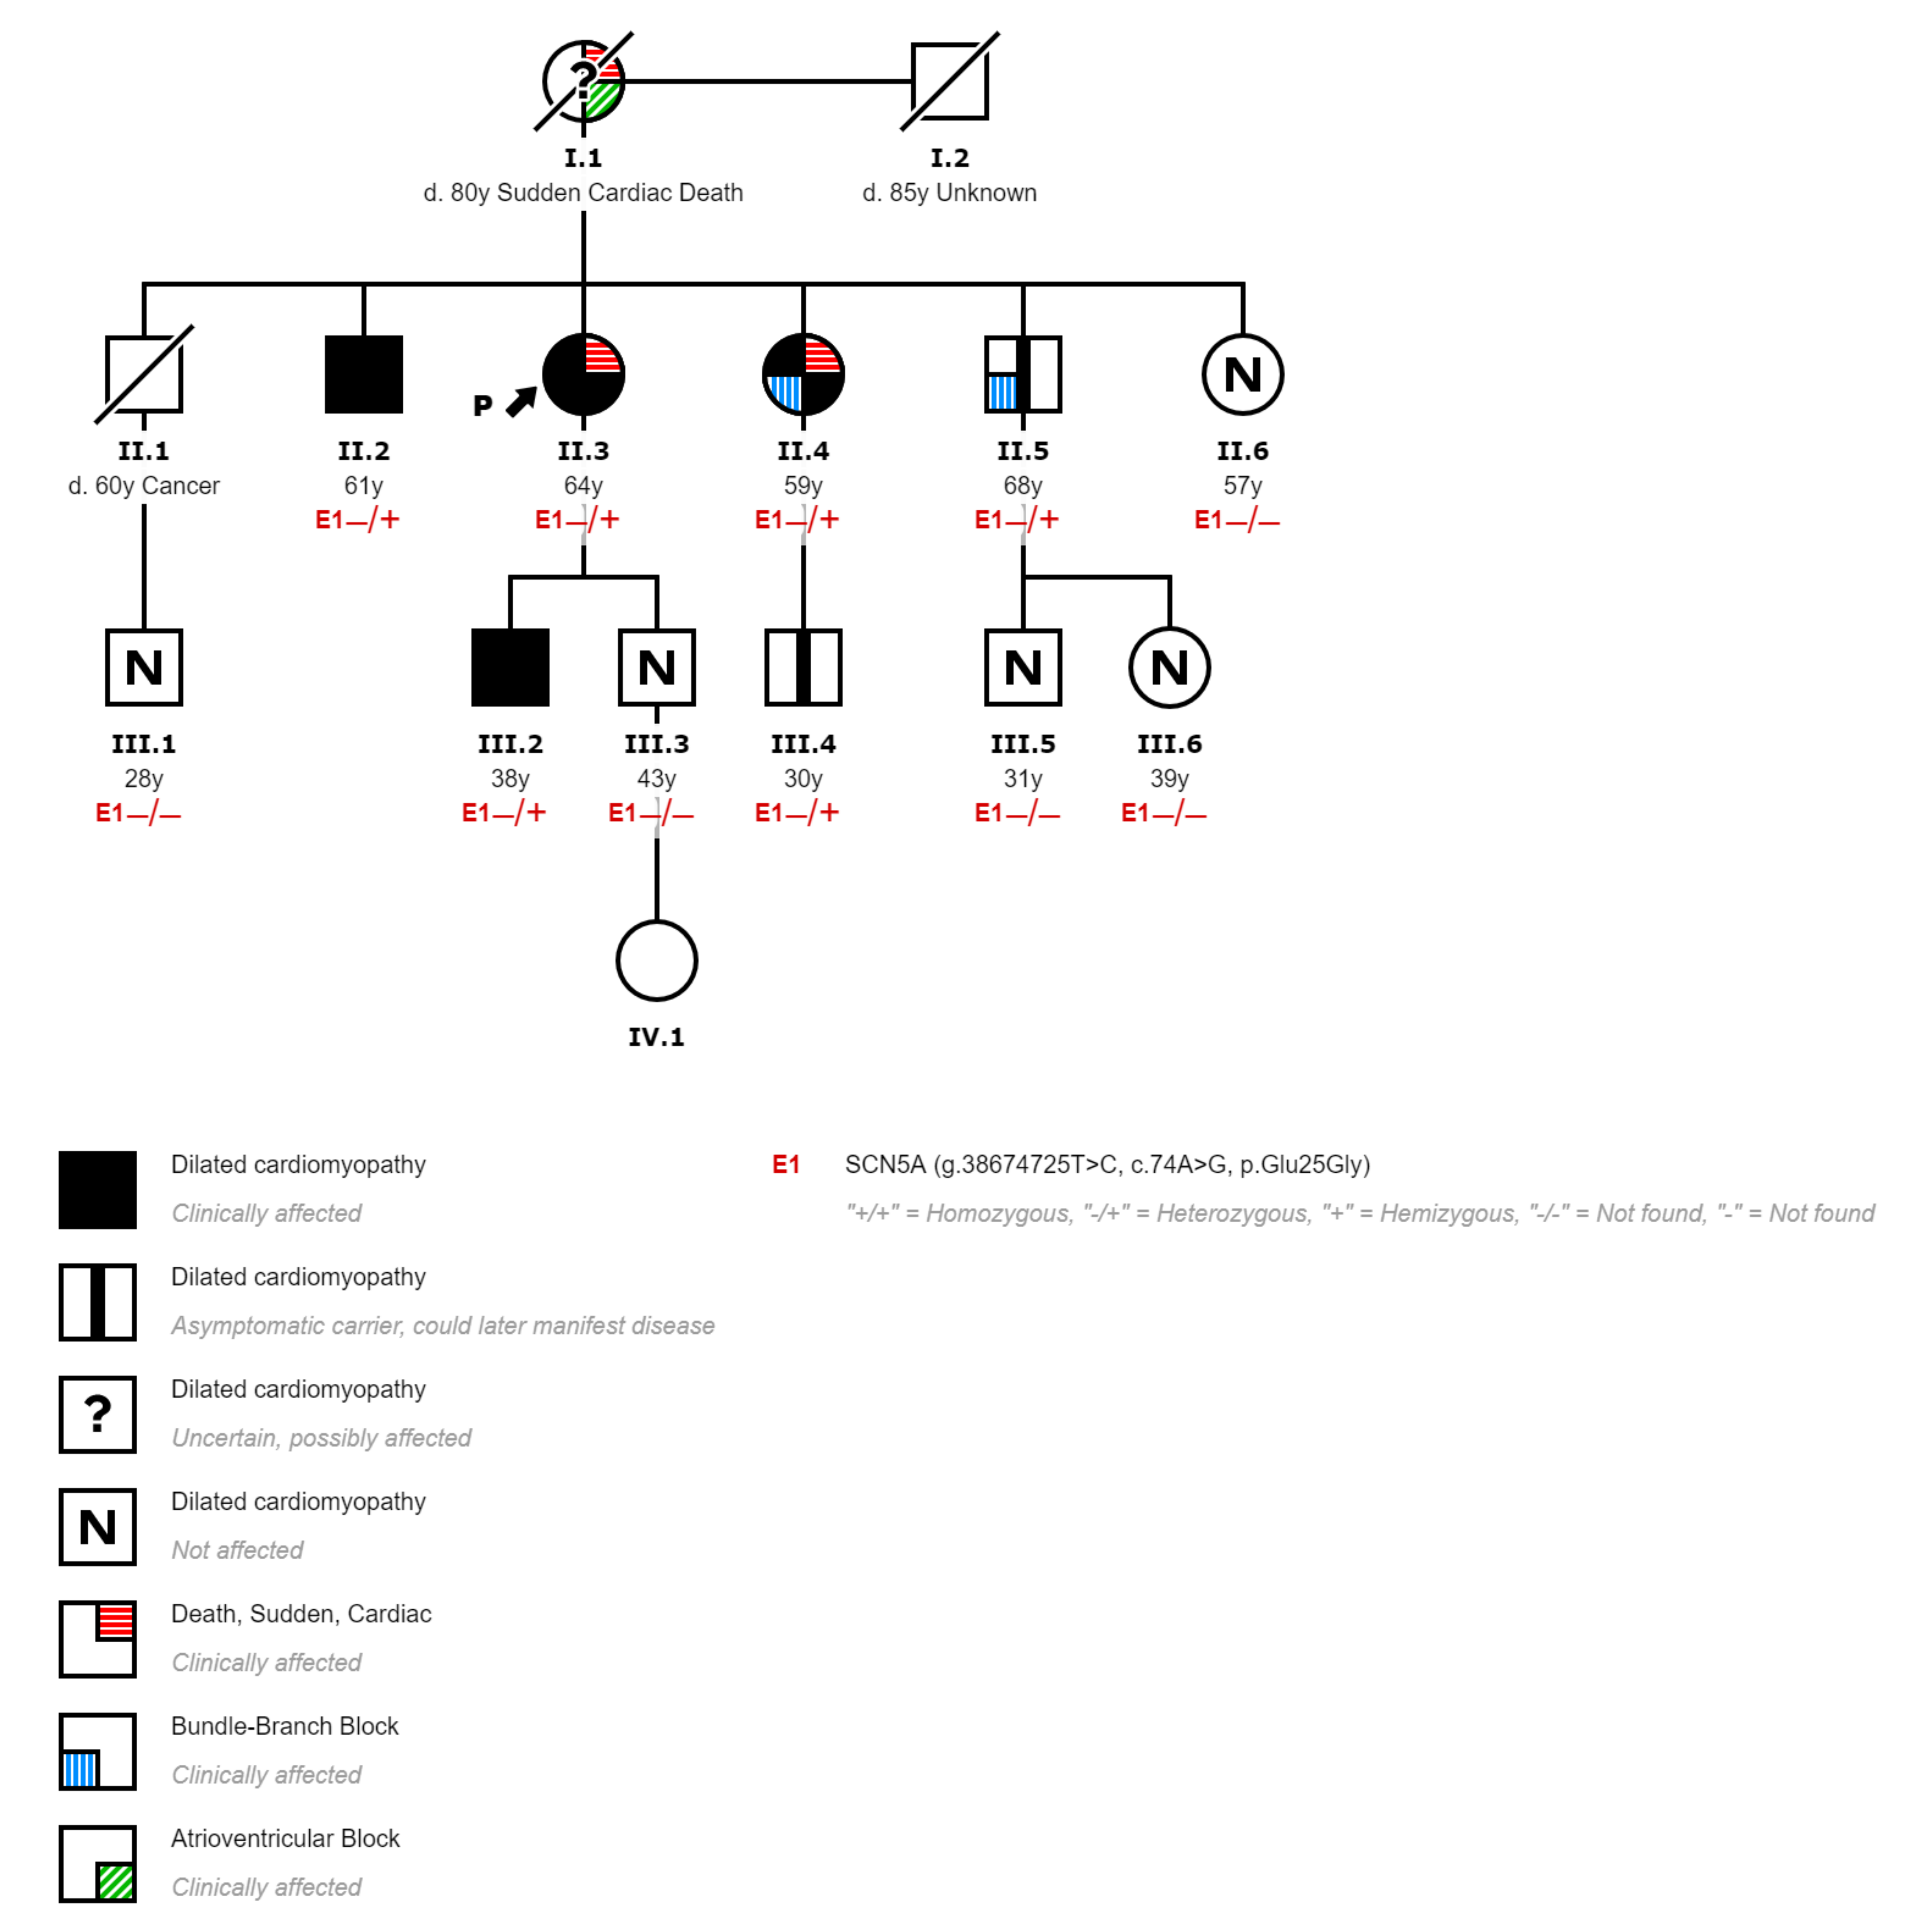

The index case is a 64-year-old woman (II-3,

Figure 1) without any known condition who resuscitated from a sudden cardiac arrest secondary to ventricular fibrillation. Her mother, who was using a pacemaker, died suddenly at the age of 80 without an autopsy report (I-1,

Figure 1). Her sister also resuscitated from a sudden cardiac arrest due to ventricular fibrillation when she was 59 years old, being diagnosed of DCM then (II-4,

Figure 1).

A cascade genetic study and phenotypical screening was performed in all living first-degree relatives (4 siblings, 2 sons, 4 niblings). The mutation was found in 3 siblings, 1 son, and 1 nephew. The carrier sister had already been diagnosed of DCM presenting with sudden cardiac arrest due to ventricular fibrillation (II-4,

Figure 1). The phenotypical study provided the following features: an ECG with left bundle branch block, a cardiac MRI with mildly dilated left ventricle with moderate systolic dysfunction (EF, 40%) and focal intramyocardial LGE in the inferoseptal wall representing 11% of left ventricular mass, and a 24 h monitorization with multiple nonsustained polymorphic ventricular tachycardia. One carrier brother was diagnosed of DCM with normal ECG, but an echocardiogram that showed a severe dilatation of the left ventricle with normal systolic function (II-2,

Figure 1). The carrier son was also diagnosed of DCM with mild dilatation of the left ventricle and mild systolic dysfunction (EF, 46%) (III-2,

Figure 1). The other carrier brother had no heart structural abnormalities at the time of the medical screening, although he had an ECG with sinus bradycardia, first-degree atrioventricular block, and right bundle branch block (II-5,

Figure 1). One nephew had no heart structural or ECG abnormalities but was also a mutation carrier (III-4,

Figure 1). Relatives with no mutation were evaluated with ECG and echocardiogram, and they did not have any pathological phenotype expression (II-6, III-1, III-3, III-5, and III-6,

Figure 1).

Therefore, all relatives with a DCM phenotype were carriers of the proband mutation, and none of the noncarriers showed clinical signs of heart disease. Accordingly, it can be assumed that the mutation segregates in the family with an autosomal dominant inheritance, and it is a likely pathogenic mutation according to ACMG/AMP guidelines [

SCN5A mutations with a marked arrhythmic behavior and a large burden of conduction defects. As discussed above, two of the family members presented with sudden cardiac arrest secondary to ventricular fibrillation and had a conduction disorder; furthermore, another carrier also had a conduction disorder. On the other hand, the deceased mother (I-1,

Figure 1) had also been treated with a pacemaker, and although we do not have genetic or phenotypic information and since the father (I-2,

Figure 1) did not have any cardiovascular disease, she must be an obligate carrier of the mutation.